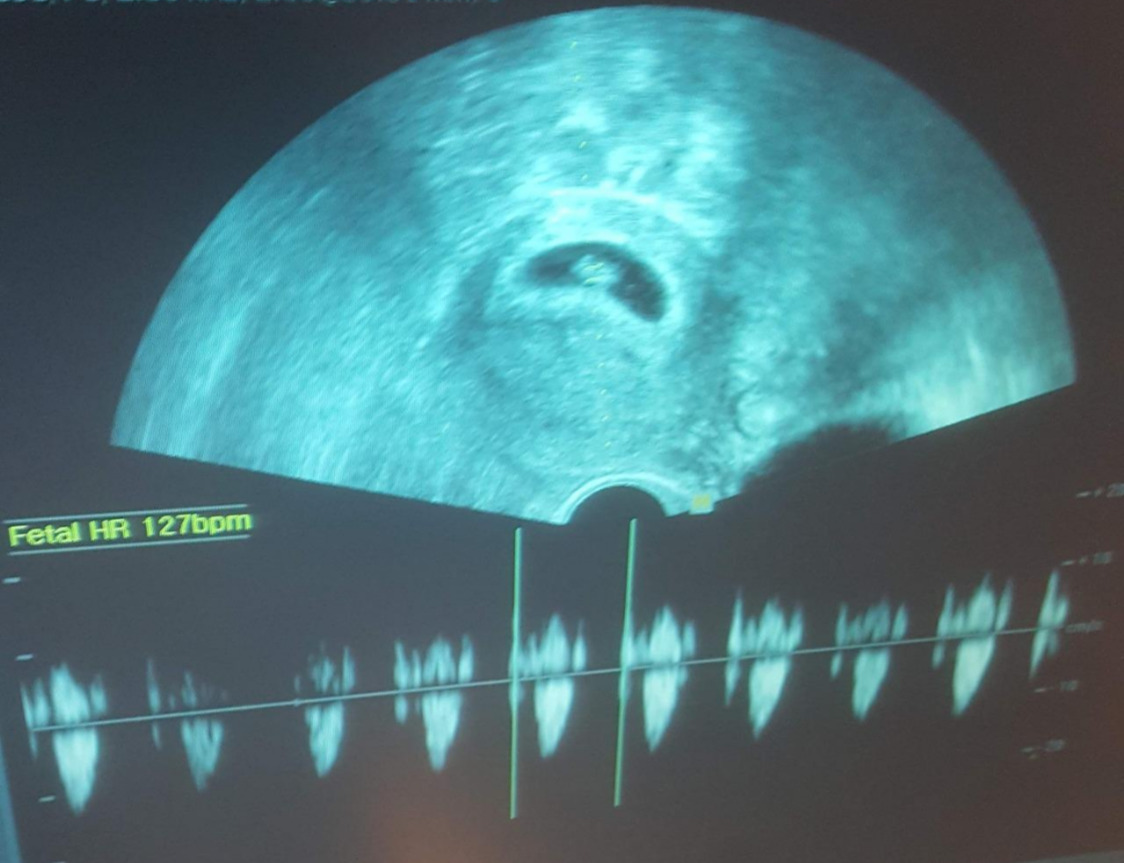

20180925_104208.jpg 처음 만난 콩알 같은 짠짠이. 기특하게도 심장이 열심히 뛰고 있었다.

아내는 5주부터 8주까지는 주 2회, 그 이후엔 주 1회씩은 병원에 가서 진료를 받고 매번 유산방지 주사도 처방받았다. 다행히도 매주 병원에 갈 때마다 상태가 조금씩 호전되어 갔고 10주 정도 되니 아기집에 핏자국은 거의 사라졌다. 12주 안정기에 접어들어 "이제 4주 후에 오시면 됩니다."라는 말을 들은 순간. 정말 "가슴을 쓸어내렸다." 이 표현이 절실하게 와 닿더라. 예전에는 심드렁했던 많은 관용어구들을 하나하나 새로 마음에 새기게 된다. 짠짠이가 생기면서.